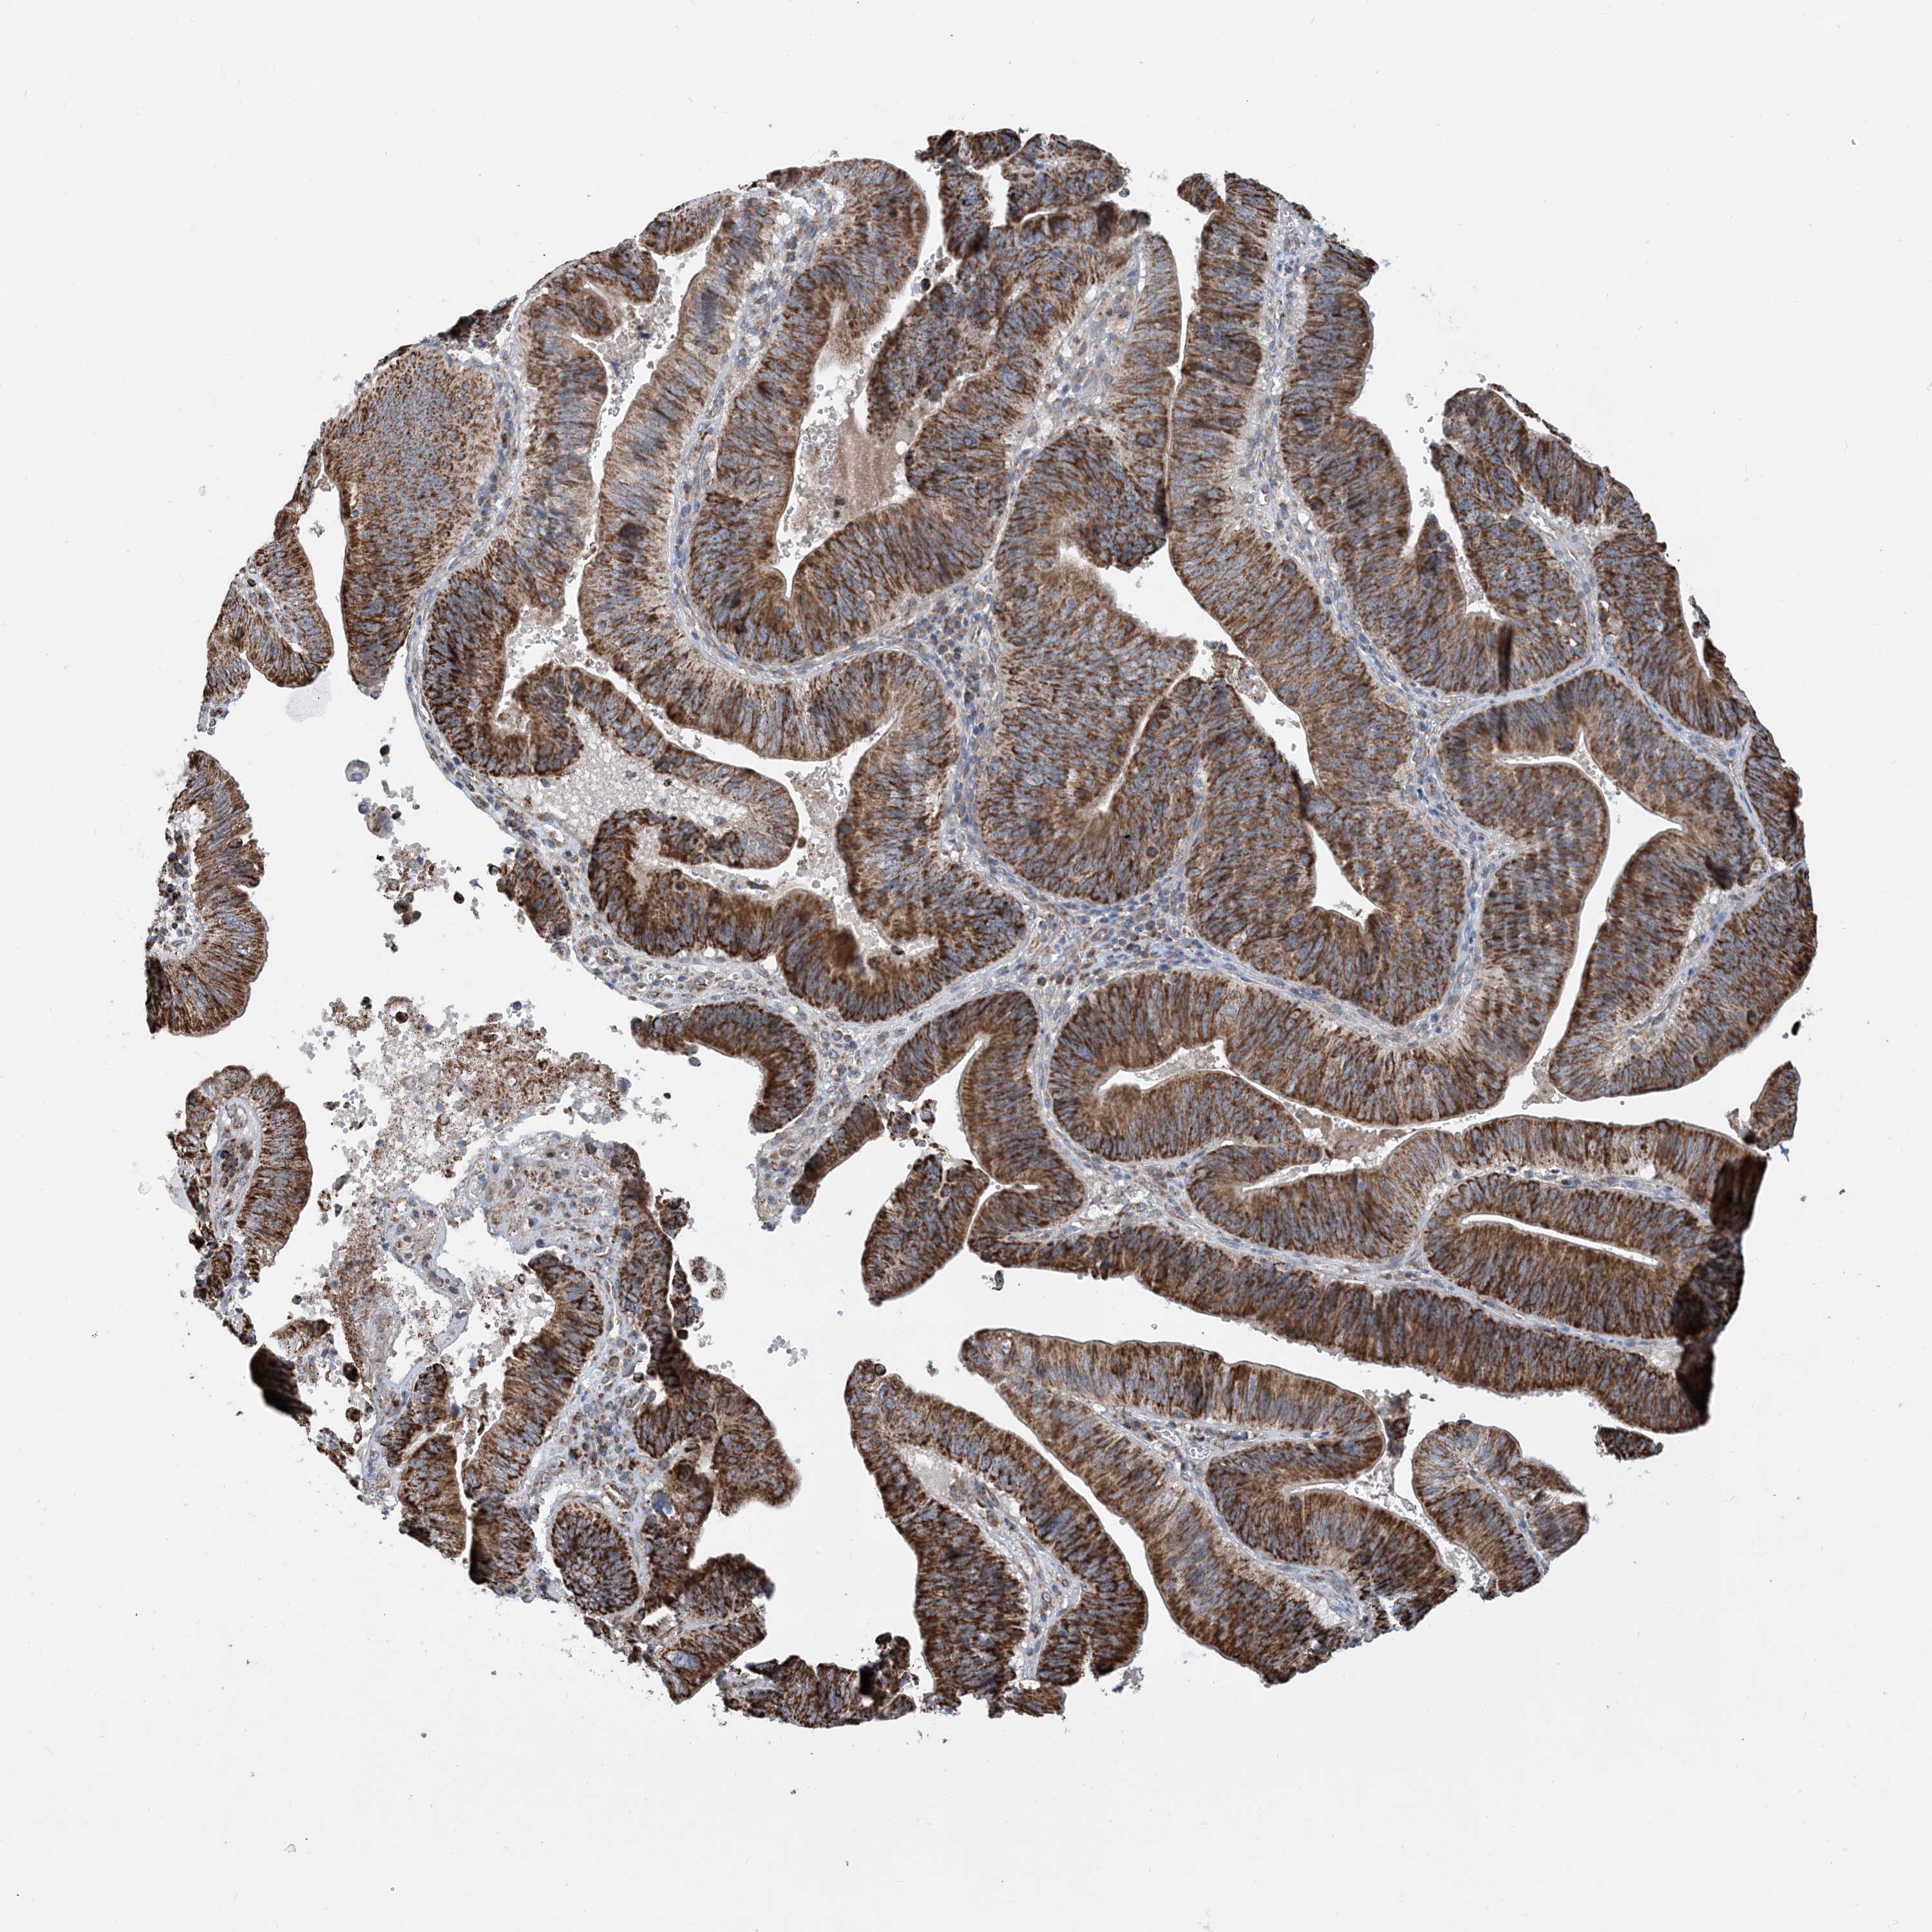

PANCREATIC CANCER - Protein expressioni

A mouse-over function shows sample information and annotation data. Click on an image to view it in a full screen mode. Samples can be filtered based on level of antibody staining by selecting one or several of the following categories: high, medium, low and not detected. The assay and annotation is described here.

Note that samples used for immunohistochemistry by the Human Protein Atlas do not correspond to samples in the TCGA dataset.

Antibody stainingi

Antibody staining in the annotated cell types in the current human tissue is reported as not detected, low, medium, or high, based on conventional immunohistochemistry profiling in selected tissues. This score is based on the combination of the staining intensity and fraction of stained cells.

Each image is clickable and will lead to virtual microscopy that enables deeper exploration of all samples and also displays staining intensity scores, fraction scores and subcellular localization as well as patient and tissue information for each sample.

Antibody HPA008755

Antibody HPA036547

Staining

High

Medium

Low

Not detected

Intensity

Strong

Moderate

Weak

Negative

Quantity

>75%

75%-25%

<25%

None

Adenocarcinoma, NOS